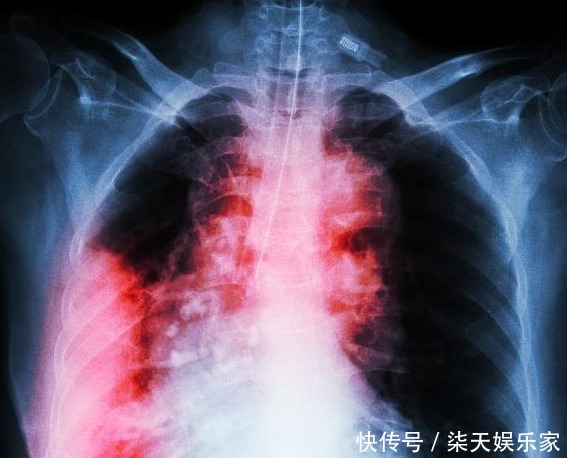

从肺癌、结肠癌到痊愈,谨记1句话,多吃2种菜,让身体健康长寿!

近些年来,社会经济与科技是发展迅速,而人们患上疾病的概率也是越来越高了,像癌症这类的大病也是越来越“放肆”,癌症患病率当然是在逐年上升了,患病人群也是逐渐趋于年轻化,人们都怕癌症!但是仅凭现代的医疗技术,还是不能够完全治愈或者是防止癌症。

87岁的国医大师王绵之,曾在一次访谈中提到过自己患上的两种癌症——肺癌、结肠癌,它当时是很坚强地抵抗过去了!在分享他的抗癌心得的时候,他告诉我们,要记住一句话,并且多吃两种菜,这样就能够起到预防癌症的作用,人才能够更长寿!一句话——开心是最好的抗癌药王绵之和我们大家一样在得知自己患上癌症之后,心情是不好的!快乐是一天,难过也是一天,既然疾病已经发生了,我们为何不调整好自己的心态去面对,王绵之的抗癌方式就是每天都让自己开心点,放空自己的身体,调整呼吸,经常笑嘻嘻……,这样的话会使自己的身体处于一种比较平静的状态中,会少一些压力,身体也会慢慢好起来。